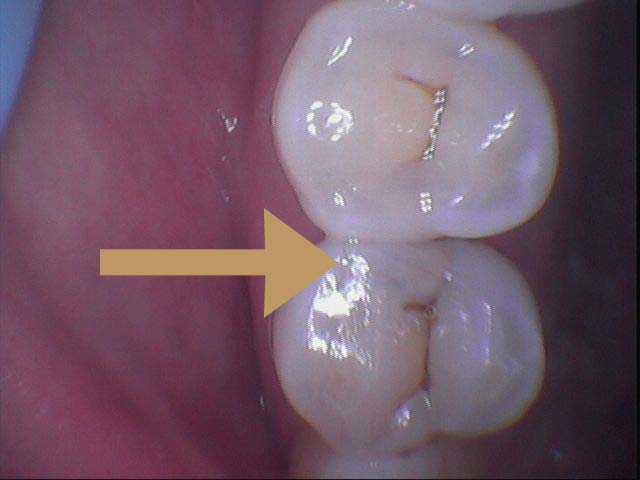

牙縫是一般患者發生蛀牙最易忽略的地方,因為難以被看見

初期蛀牙,可以採取樹酯填補,如以下步驟:

但是樹酯因為強度不足往往一段時間後,產生邊緣龜裂,與二次蛀牙這時候蛀牙範圍往往會比第一次更大,可以使用3D齒雕作修復, 提供牙齒良好的強度與美觀。